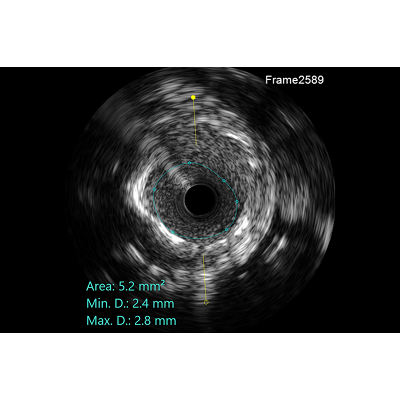

Co-register real time between angiography and lVUS/OCT with lV-LINQ to obtain adetailed view of the lesion and its exact location in the coronary tree.By using just two angiograms (one with and one without contrast), co-registration can beperformed with every lvUS or OCT system.

Co-registered view between angiogram and lVUs/OCT pullback